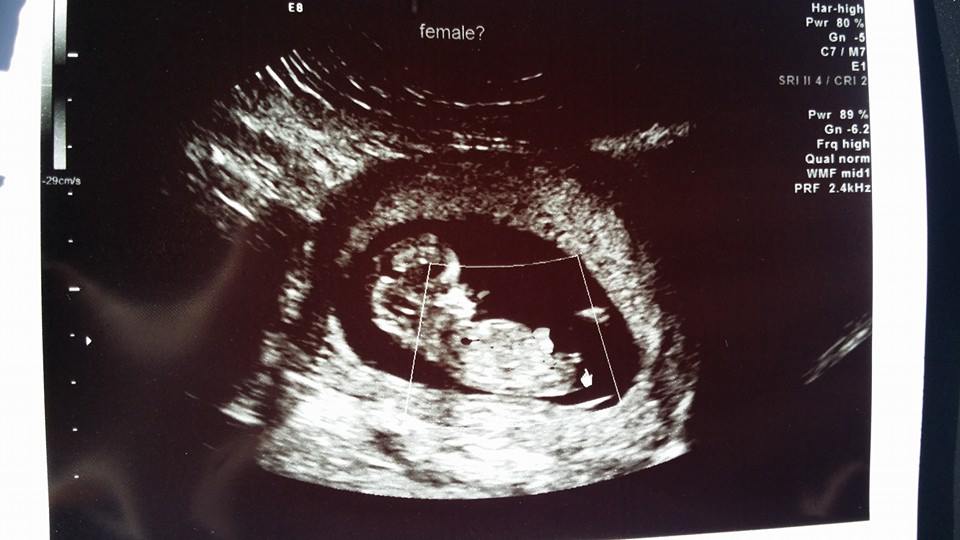

12 week ultrasound! I know its too early to know for sure but the tech said she has a strong feeling it is a girl!!!:) any thoughts?

Confirmed girl! :)Attachment 19323